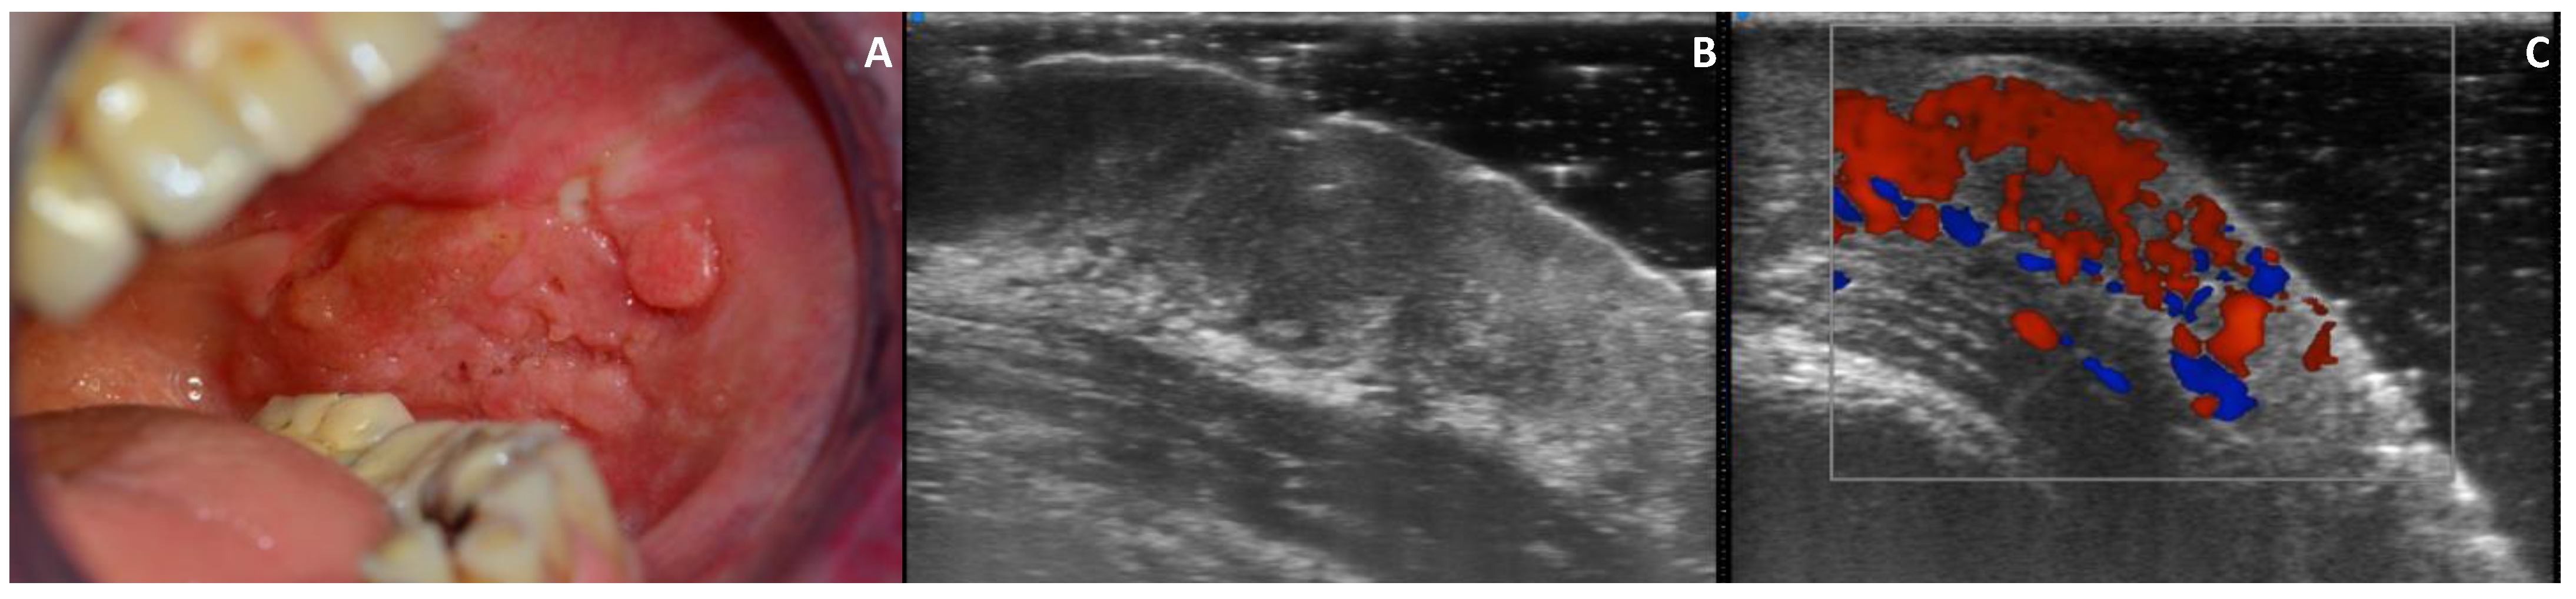

3.4. Echogenicity

3.5. Vascularization